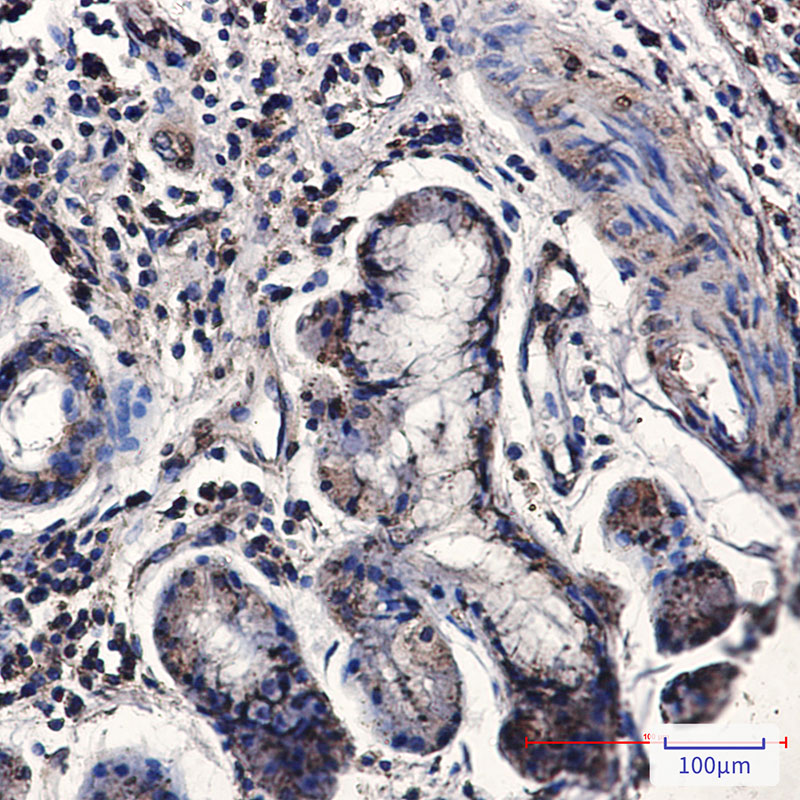

- Immunohistochemistry analysis of paraffin-embedded Human lung cancer using CNOT7 antibody. High-pressure and temperature Sodium Citrate pH 6.0 was used for antigen retrieval.